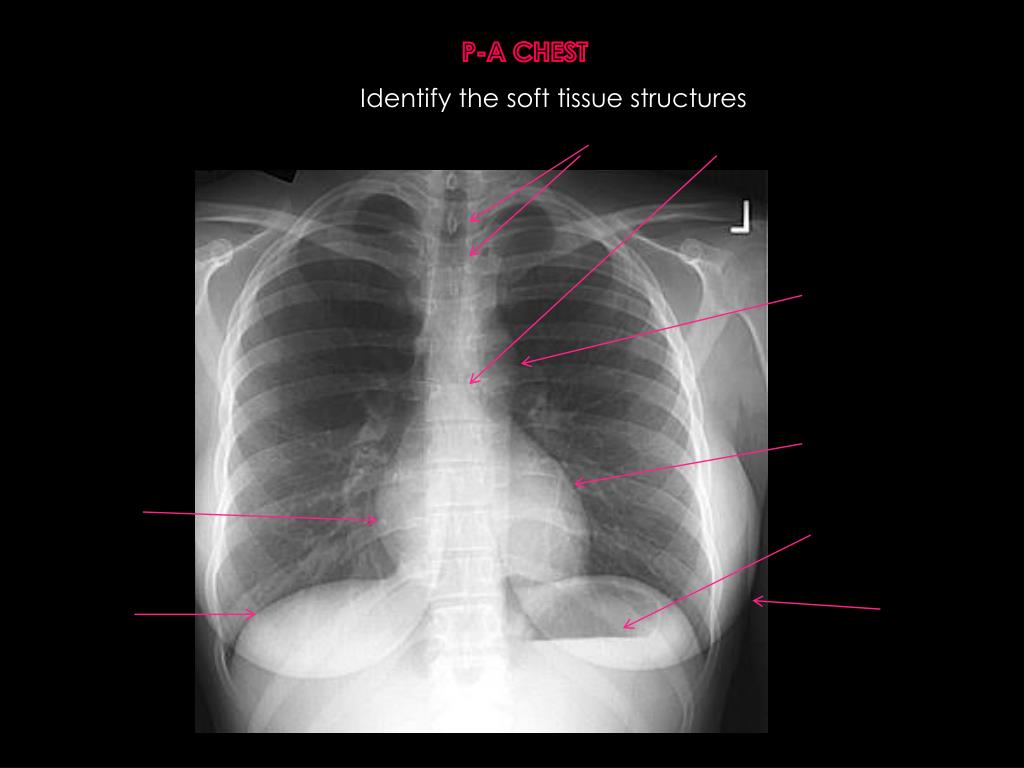

5. P-A CHEST Identify the soft tissue structures

6. P-A CHEST Identify the soft tissue structures Tracheal air shadow Lt main stem bronchus Aortic Knob Lt ventricle Rightatrium Magenblasse Right hemidiaphram Breast shadow